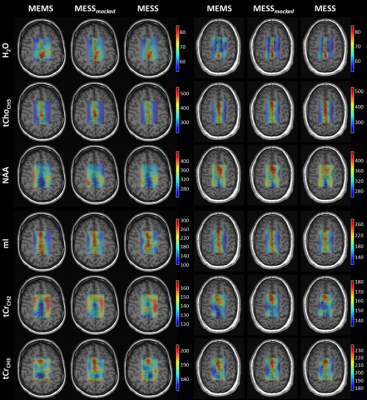

Estimated concentrations and T2 values for a subset of metabolites are reported spectrum-by-spectrum throughout the VOI (Fig.2). The evaluation considers fitting on a zero-filled k-space grid with cropped voxels at the edges to minimize partial volume effects (8x8 voxels). Values and trends are comparable. The figure includes fit uncertainties (CRLBs). Precision for concentration and T2 estimates is equivalent or better for MESS (c.f. CRLBs, Fig.2-red).

Fig2.: Estimates and uncertainties (CRLBs) for tissue concentrations (NAA: N-acetylaspartate, tCho: total choline and mI: myo-inositol) and T2s (NAA: N-acetylaspartate-singlet at 2ppm, tCho-CH3: tCho singlet at 3.2ppm and mI: myo-inositol). Estimates from MEMS (blue), MESS-mocked (orange), and MESS (red) overlap nicely, and their oscillation throughout the VOI reflects WM and GM variation. CRLBs report higher precision for MESS. (Right) Voxel numbering referenced to the VOI.

Fig.4: T2 maps in millisecond units [ms] of parenchymal water and a subset of metabolites, reported for two subjects and the three methodologies. H2O: parenchymal water, tCho-CH3: total choline singlet at 3.2ppm, NAA: N-acetylaspartate singlet at 2ppm, mI: myo-Inositol, tCr-CH2: total creatine methylene resonance at 3.9ppm and tCr-CH3: tCr methyl resonance at 3ppm. Maps are displayed with zero-filling in spatial domain with cropped voxels at the edges (20x20 voxels).